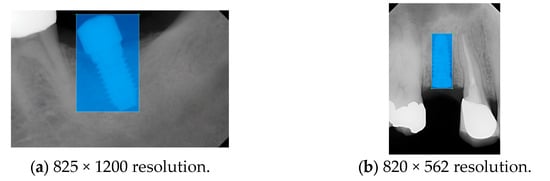

2.3. PA Resolution Enhancement

2.3.2. Lanczos Interpolation